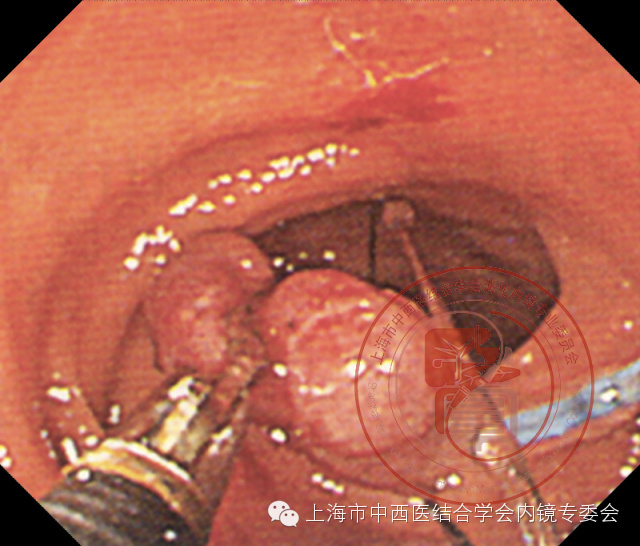

带蒂息肉

阻断蒂部血供